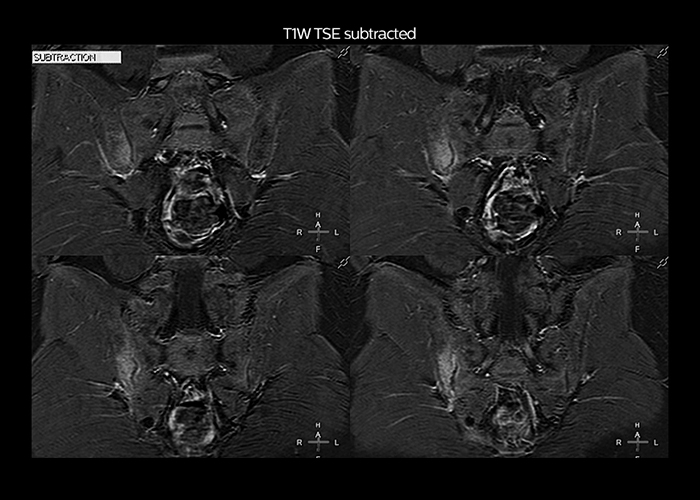

“To avoid coil changes we plan examinations of similar anatomies back to back, such as head and spine. Multiva helps us here a lot because coils don’t need to be changed frequently. Moreover, thanks to parallel imaging technology and 16-channel HeadSpineTorso and 8-channel MSK coils we are able to achieve excellent image quality. In this way Multiva helped us to increase both image quality and productivity.”

“Neurological cases, such as brain and spine imaging, represent the largest share in our MR scanning, followed by musculoskeletal cases. In general, we use simple and basic imaging protocols. But occasionally, we use advanced techniques for problematic cases if necessary.